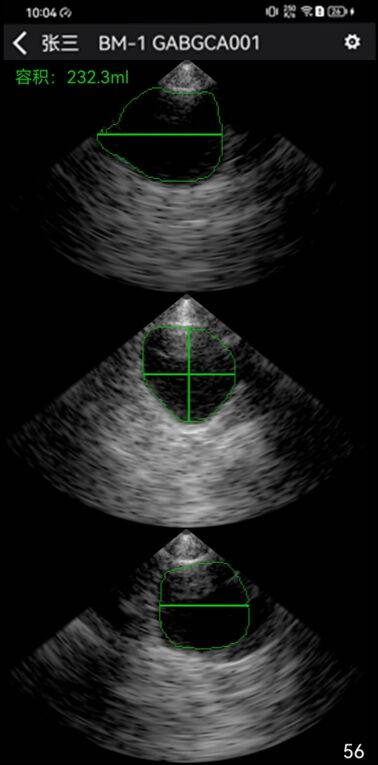

B1尿量监测器底部的三个多阵元相控阵探头,通过不同角度扫描膀胱并进行图像融合形成立体图像,计算出尿量。

· 精准度高:立体图像计测精准,且不管什么体位都能测量